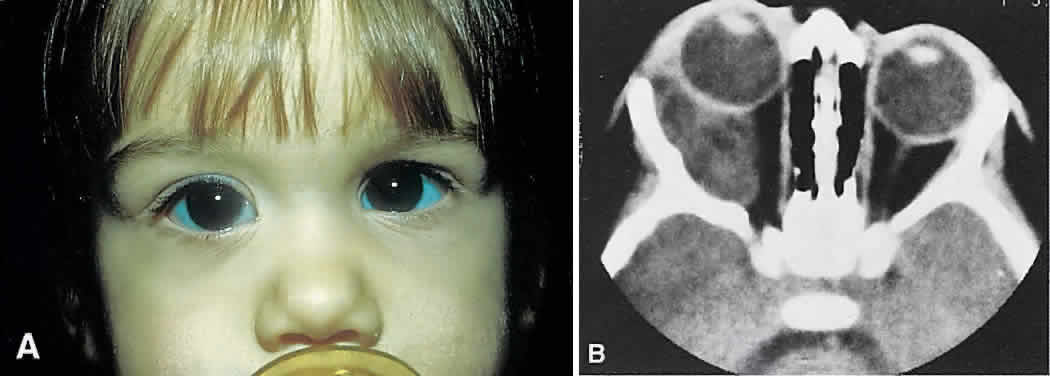

Fig. 20. A. Right proptosis was noted only a few weeks before presentation in this 3-year-old

girl. B. A long-standing process is suggested by overall expansion of the bony

orbit and local fossas on the orbital faces of the zygomatic and sphenoid

bones. Keratin clumps and glandular products within the dermoid cyst

have different radiodensities. Fig. 20. A. Right proptosis was noted only a few weeks before presentation in this 3-year-old

girl. B. A long-standing process is suggested by overall expansion of the bony

orbit and local fossas on the orbital faces of the zygomatic and sphenoid

bones. Keratin clumps and glandular products within the dermoid cyst

have different radiodensities.

|